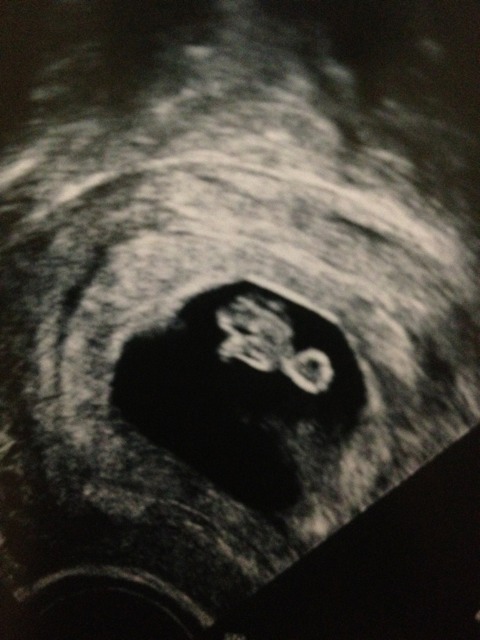

Attachment 5570

Any guesses?

Transvaginal. Feel like another boy but ultrasound of first child is way different!

Looks to me like the placenta is on the right side of the pic if was turned the right way, so that would be a girl. Just my guess though.